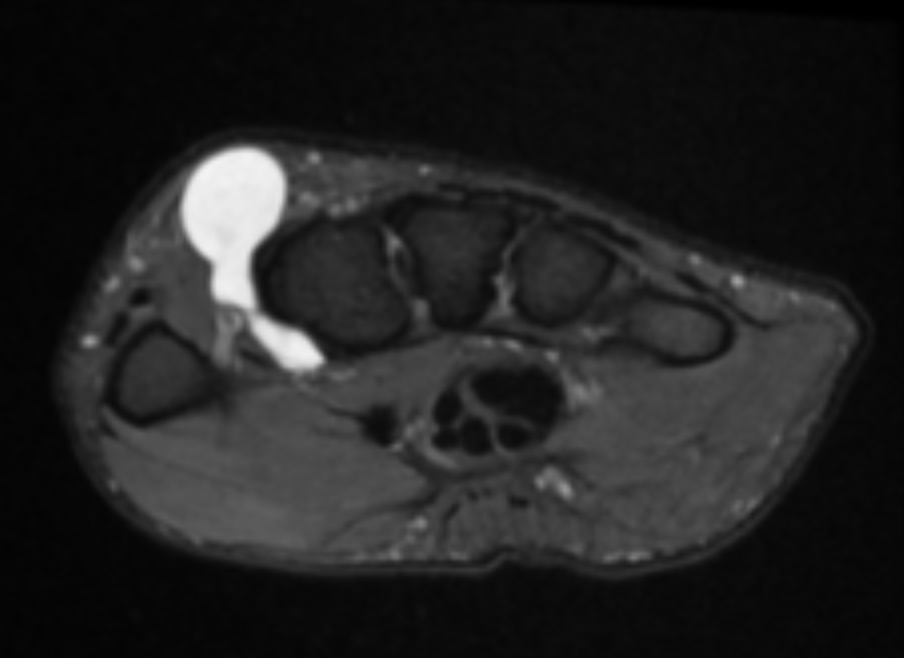

Describe the pathology (Ax T2 FS).

Tenosynovitis